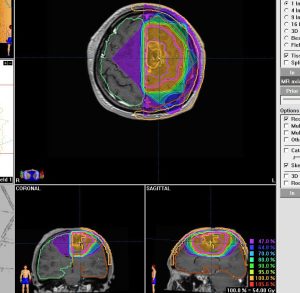

expanding, solid 固形腫瘍的なもの

壊死ではない「のう胞」を伴い,ガドリニウムで強く増強されます。グレード 4 (膠芽腫)と間違えるようなものです。しかし,のう胞はありますが中心壊死がありません。

腫瘍を大部分摘出できるので,積極的な摘出術をして,手術後には放射線化学療法を加えます。この例では,手術後の放射線治療計画の領域が狭ければ,60グレイを使用できる部位です。